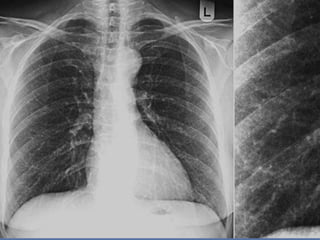

CRITERIOS DE EVALUACION RX.

TX.

 Pulmones desde ápex

hasta senos costo

diafragmáticos

   Pulmones y corazón sin

rotación.

   10 pares de costillas.

   Sombra área de la

tráquea centrada sobre

la columna.

   Balance en los

contrastes de la imagen

(exposición adecuada).

INTERPRETACION

 Revisar estructuras

óseas.

   Partes blandas.

   Espacios intercostales.

   Parénquima pulmonar

   Nivel de los senos

costodiafragmaticos.

   Neumatización.

   Trama alveolo-pulmonar

   Silueta cardiaca

   Cayado aórtico.

CRITERIOS DE EVALUACIONRX. TX.  Pulmones desde ápex hasta senos costo diafragmáticos  Pulmones y corazón sin rotación.  10 pares de costillas.  Sombra área de la tráquea centrada sobre la columna.  Balance en los contrastes de la imagen (exposición adecuada).

INTERPRETACION  Revisar estructuras óseas.  Partes blandas.  Espacios intercostales.  Parénquima pulmonar  Nivel de los senos costodiafragmaticos.  Neumatización.  Trama alveolo-pulmonar  Silueta cardiaca  Cayado aórtico.